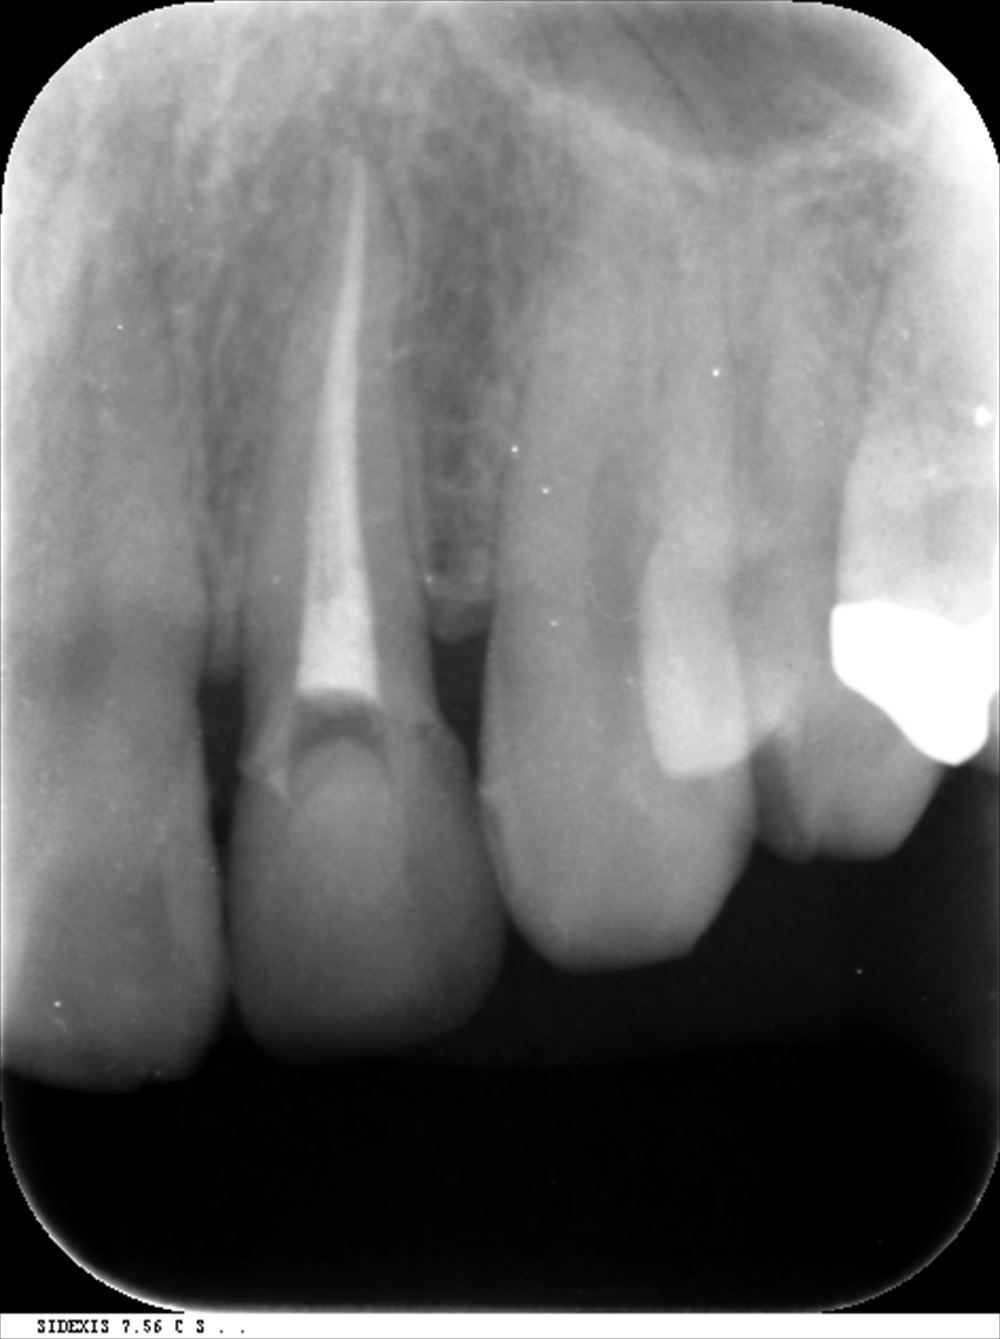

前歯の根管治療。ラバーダム後

この裏にガッタパーチャがある。なかなかとれない。

格闘20分 取れた!!

綺麗になったので根管充填

術前 根管充填が足りず感染がある。

術後 根の先まできっちり。